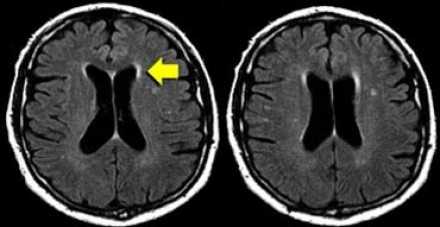

На магнитно-резонансных томограммах продемонстрирована нормальная возрастная картина: расширение борозд, перивентрикулярные «шапочки» (желтая стрелка), «полосы» и точечные очажки в глубоком белом веществе.

Перивентрикулярные «шапочки» представляют собой области, дающие гиперинтенсивный сигнал, расположенные вокруг передних и задних рогов боковых желудочков, обусловленные побледнением миелина и расширением периваскулярных пространств. Перивентрикулярные «полосы» или «ободки» это тонкие участки линейной формы, расположенные параллельно телам боковых желудочков, обусловленные субэпендимальным глиозом.

- Перивентрикулярные «шапочки» и «полосы»

- Умеренно выраженная атрофия с расширением борозд и желудочков мозга

- Точечные (и иногда даже диффузные) нарушения нормального сигнала от мозговой ткани в глубоких отделах белого вещества (1-й и 2-й степени по шкале Fazekas)